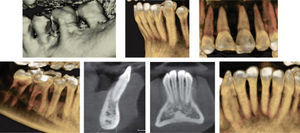

In the cephalometric analysis she was a skeletal class III, mesocephalic, with a concave profile, neutral growth and lower lip protrusion (Figure 1). In the panoramic radiograph she presented 28 erupted permanent teeth, loss of alveolar crests and a root-crown ratio of 3:1 (Figure 2).

Facially, she presents a concave profile, mesofacial pattern, decreased upper facial third, asymmetry, neutral smile, lip competence and a slightly everted lower lip. Upon clinical examination and intraoral analysis, it was observed bilateral molar class III, a canine class III, a 3mm overbite, -2mm overjet, moderate lower dental crowding, dental midline deviation, ovoid upper and lower arch form, unilateral anterior and posterior crossbite and controlled generalized chronic periodontitis (Figures 3 at 5).

TREATMENT PROGRESSTreatment was begun with the placement of fixed appliances, 0.022” slot Roth system, in the upper arch. The Department of Periodontics conducted the scaling and root planning in the lower anterior area and subsequently, placed a free gingival graft. A month later fixed appliances were placed in the lower dental arch thus beginning the leveling and alignment with the corresponding archwires (Figure 6). Three segments were formed throughout this phase: one anterior segment and two posterior ones. After the segments were formed a single keyhole loop (SKL) archwire was placed in the lower arch maintaining a segment with ligature wire from lower first molar to canine on both sides. The archwire was activated in the following appointment with a Suzuki retroligature to begin space closure (Figure 7A).